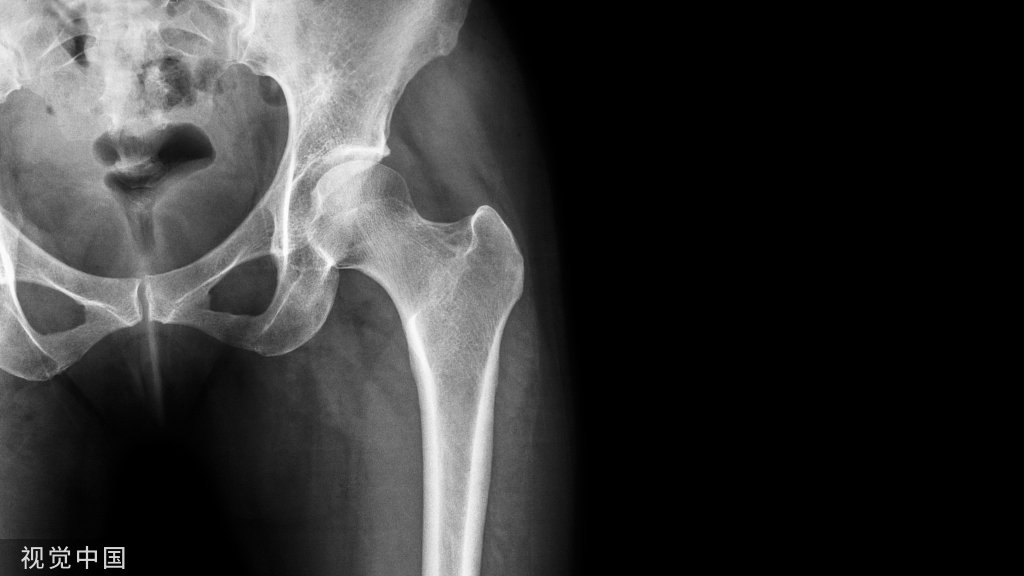

采用单一外侧入路,由浅至深依次显露损伤的LUCL止点、桡骨头骨折、冠状突骨折及前关节囊,然后再由深至浅,由内至外依次对冠状突+前关节囊、桡骨头、外侧副韧带(lateral collateral ligament, LCL)复合体+伸肌总腱起点等受损结构进行修复。以外上髁作为解剖学标志,沿髁上嵴—外上髁—桡骨头中点连线做一4~6cm的切口,皮下游离。此时通常在外上髁中线后方发现软组织撕脱,形成裸区,从原始裂口进入,沿肱骨外上髁和桡骨头中线劈开指总伸肌,远端至桡骨颈部即可,避免损伤桡骨转子下方的桡神经深支;近端剥离外上髁中线前方的肱桡肌和桡侧腕长短伸肌,向前拉开前关节囊(如图1,经外侧入路可清晰显露桡骨头和冠状突骨折)。即使桡骨头骨折块小或相对完整,也可通过该入路很好地显露和处理冠状突,桡骨头置换时显露更清楚。